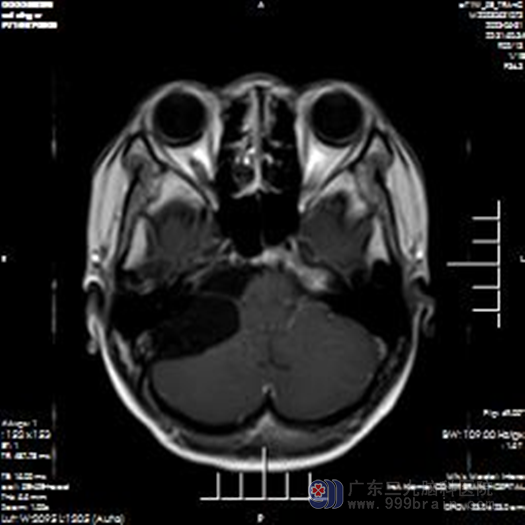

近日26岁的蔡女士,在家中休息突然出现头痛头晕,呕吐一次,蔡女士怀着焦虑紧张的心情,随即就诊于当地诊所,诊断“胃炎”。吃了胃药一段时间以后发现症状并未缓解, 甚至还出现了加重的症状,这让蔡女士一家都很是担心。为进一步诊疗,终于在家人的劝说下来到了三九脑科医院就诊,诊断出“右侧桥小脑角区占位”,随即收入神经外十科。

让我们来了解一下桥小脑角区占位:桥小脑角区是由前内侧的脑桥外缘、前外侧的岩骨内缘以及后下方的小脑半球前外侧缘构成一个锥形窄小的空间。包含了听神经、面神经、三叉神经及小脑前下动脉等,如果局部出现肿瘤或其他占位,会导致患者出现桥小脑角综合征,桥小脑角综合征主要症状是耳鸣,进行性耳聋、面瘫、同侧肢体的共济失调。表皮样囊肿好发于脑部的桥小脑角、鞍区和颞极等处,它囊壁薄,由一层表皮组织形成,囊内有上皮碎屑,角蛋白和胆固醇组成。囊肿不规律,沿缝隙生长是它特点。常见于后颅窝,其次,为额叶底部或颞极。如果形成脑积水导致颅内压增高还会出现头痛、恶心、呕吐。因为症状和胃炎很像似,患者常常觉得没什么问题,以为是胃炎。很容易忽略掉,从而影响患者后续病情治疗。

患者入院以后,欧阳辉教授带领神经外十科医生团队,对患者进行详细的检查,可考虑行“右侧桥小脑角区占位切除术”,并为患者制定了手术方案。实施手术:采用右侧乙状窦后入路,采用全麻麻醉方式行右侧桥小脑角区占位切除术,在医生的沟通下,家属同意手术。